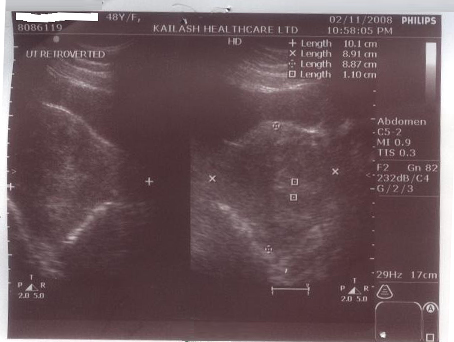

After the treatment:

Her Ultrasound was repeated in November 2008, which showed a decrease in the size of the fibroid, but the endometrial thickness was a matter of concern. With continued treatment latest ultrasound, done in March 2009, showed a marked reduction in the size of the fibroids and also the endometrial thickness came down to 6 mm.